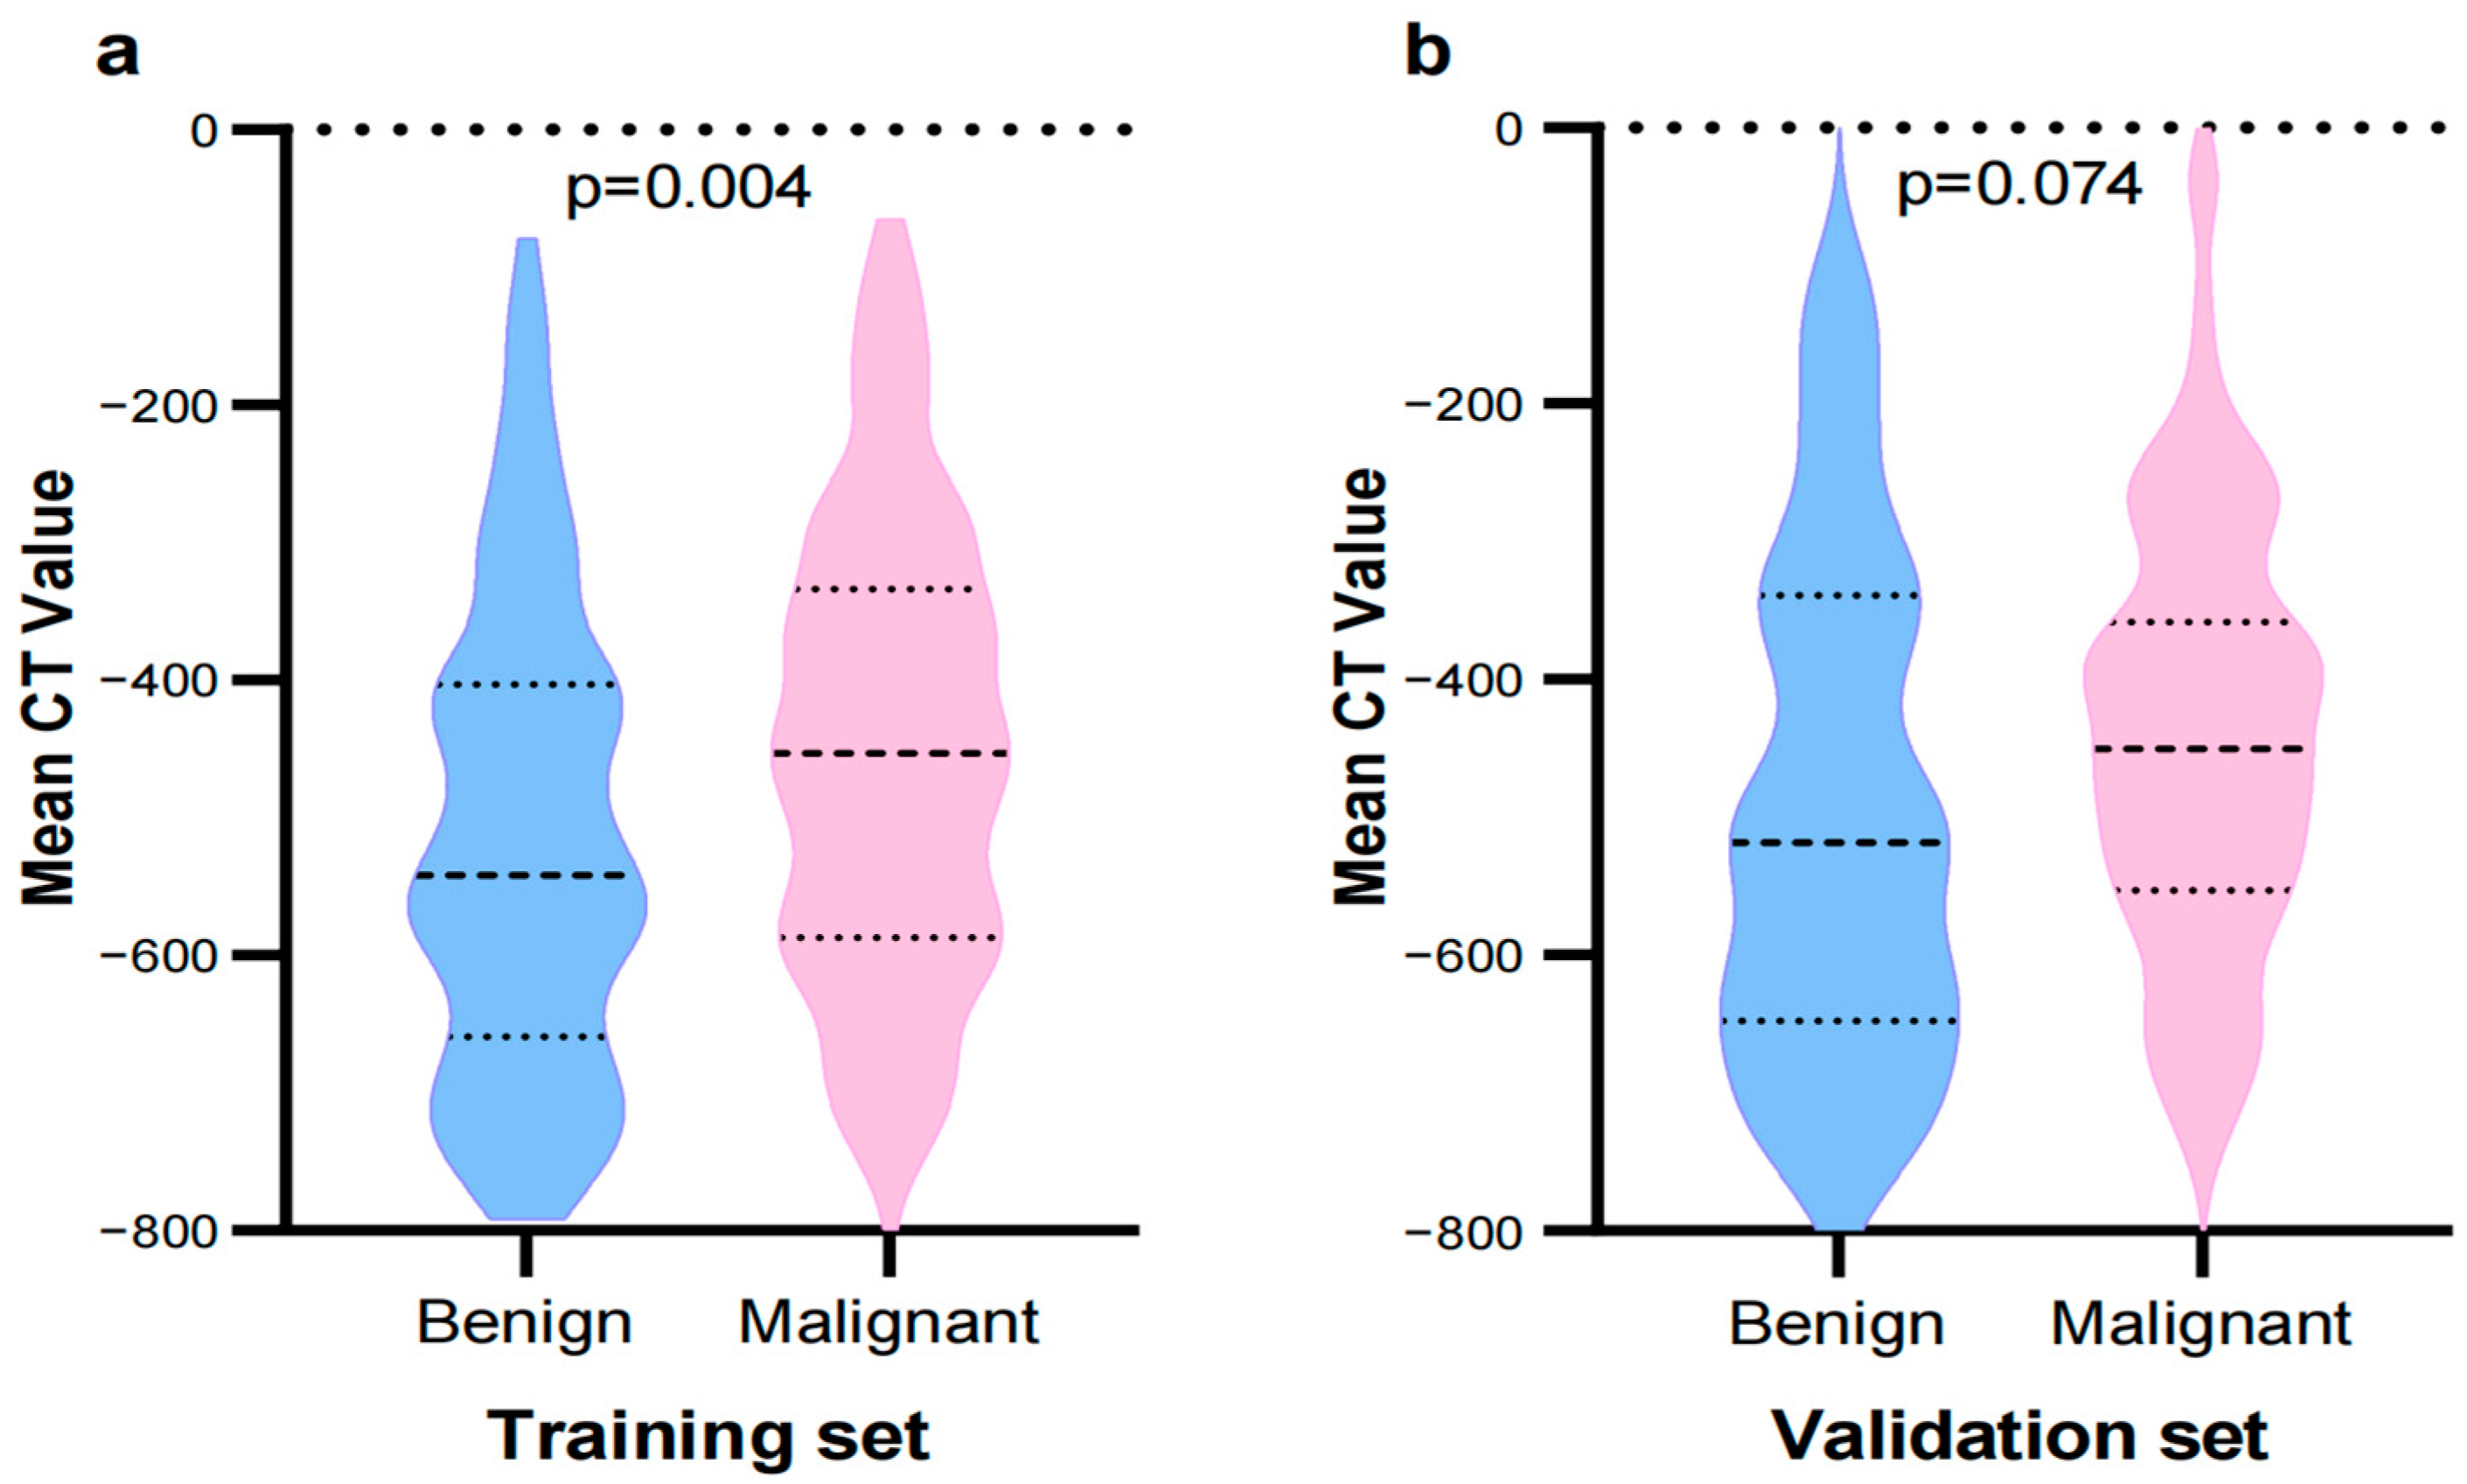

3.1. General Information and CT Imaging Features

| Mean CT value, M (Q1, Q3) | −477.30 (−599.59, −356.35) | −541.56 (−647.60, −403.13) | −452.90 (−585.46, −337.68) | Z = −2.85 | 0.004 |